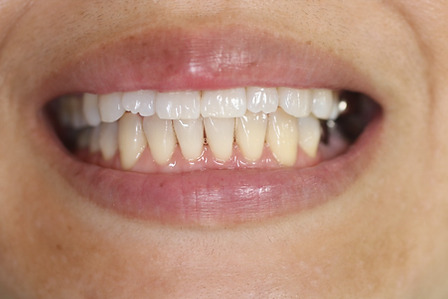

1矯正・マウスピース【治療例2】

治療前

治療後